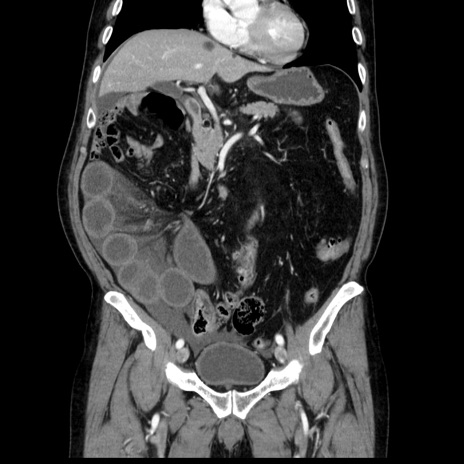

症例30(冠状断像)

【症例】80歳代男性

【主訴】臍周囲痛

【現病歴】約6時間前から臍下部痛が出現。次第に腹部膨隆・背部痛も生じてきたため来院。背部痛の場所は変化しない。

【既往歴】腎盂腎炎

【身体所見】意識清明、BT 36.3℃、BP  131/87mmHg、P 87bpm、SpO2 100%(RA)、臍周囲自発痛・圧痛あり、反跳痛なし、自発痛部位に一致して板状硬あり、腹部膨隆、腸雑音減弱、CVA tenderness両側陰性。

【データ】WBC 19600、CRP 0.33